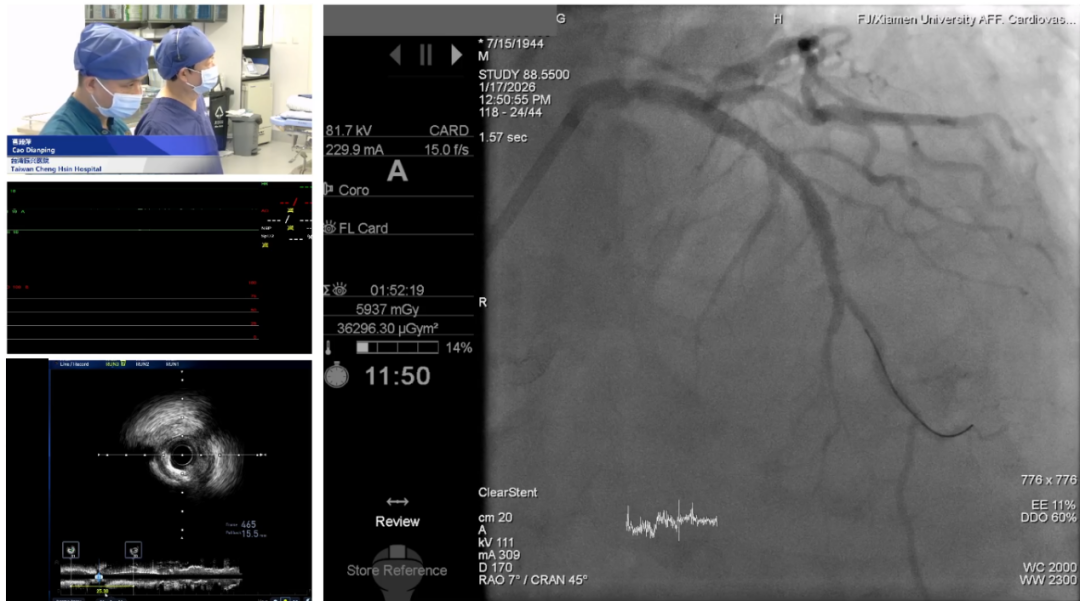

手术2:Rota-Tripsy策略治疗严重钙化病变

曹殿萍教授及厦门大学附属心血管病医院手术团队

随后,台湾振兴医院曹殿萍教授团队协同厦门大学附属心血管病医院手术团队带来一例严重钙化病变的治疗策略演示。患者为81岁男性,因胸痛半年、近一周加重就诊,既往合并长期高血压、慢性肾病并长期透析及脑梗死病史。急诊冠脉造影显示前降支开口重度狭窄合并中段弥漫狭窄,伴多发重度钙化;回旋支近段中度狭窄;右冠第一转折处严重钙化。患者急诊阶段已置入IABP支持,并通过旋磨成功完成右冠钙化病变的支架治疗,本次手术重点处理前降支严重钙化病变。术者操作工作导丝行走至LAD远端后推送微导管跟进,并借助延长导管增强支撑力完成旋磨导丝交换,随后应用偏心旋磨逐渐提速、缓慢分段方式,对前降支开口至中段的严重弥漫钙化组织进行了充分预处理,随后依据IVUS影像提示,主动运用Rota-Tripsy策略,采用冲击波球囊进一步修饰钙化,最终依据病变情况选择近中段串联植入支架、远端药物球囊完成治疗。该病例充分展示了腔内影像技术对钙化病变的充分评估及Rota-Tripsy策略下对弥漫性严重钙化病变的有效修饰,实现精准介入诊疗。